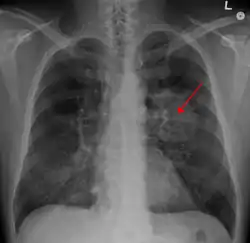

| نمونهای از تومور موجود در ریه که توسط پیکانی بر روی رادیوگرافی قفسه سینه نشان داده شدهاست. | |

شایعترین علت سرطان ریه قرار گرفتن در معرض دود دخانیات[2] برای مدتی طولانی دلیل ۹۰٪ سرطانهای ریه است.[1] درصد ابتلا به سرطان ریه در افرادی که سیگار نمیکشند ۱۵٪ است،[3] و دلیل این موارد اغلب ترکیبی از عوامل ژنتیکی،[4] گاز رادون،[4] آزبست،[5] و آلودگی هوا[4] از جمله دود سیگار فرد ثالث مربوط میشود.[6][7] ممکن است سرطان ریه در رادیوگرافی قفسه سینه و مقطعنگاری رایانهای (سیتی اسکن) قابل تشخیص باشد. تشخیص با یک بافتبرداری[8] که اغلب از طریق برونکوسکوپی یا راهنمای سیتی انجام میشود، قابل تأیید شدن است. درمان و نتایج طولانی مدت به نوع سرطان، مرحله (شدت گسترش) و سلامت کلی فرد، که از طریق وضعیت عملکرد سنجیده میشود، بستگی دارد.

انجام یک رادیوگرافی قفسه سینه یکی از نخستین مراحل تحقیقی است که باید در صورت گزارش نشانههایی توسط فرد که ممکن است دال بر سرطان ریه باشد، صورت پذیرد. این کار میتواند یک توده مشخص، گشادگی میانسینه (که میتواند بیانگر گشادگی غدد لنفاوی واقع در آنجا باشد)، آتلکتازی (جمع شدن ریه)، التهاب ریه، یا ترشح پرده جنبی را آشکار نماید.[2] تصویربرداری سیتی نوعاً به منظور ارائه اطلاعات بیشتر در مورد نوع و درجهٔ بیماری مورد استفاده قرار میگیرد. نایژهبینی یا بافتبرداری هدایت شده توسط سیتی اغلب برای نمونهبرداری تومور برای بافتآسیبشناسی مورد استفاده قرار میگیرد.[10]

سرطان ریه اغلب به صورت یک توده ریوی منزوی بر روی یک پرتونگاری قفسه سینه ظاهر میشود. لیکن تشخیص افتراقی آن بسیار گستردهاست. بسیاری از بیماریهای دیگر نظیر سل، عفونتهای قارچی، سرطان دگردیس، یا التهاب سازماندهنده ریه نیز میتوانند چنین نمودی را نتیجه دهند. از جمله علل کمتر رایج «توده ریوی منزوی» میتوان به هامارتومها، کیستهای برونکوژنیکها، ورمهای غدهای، ناهنجاری شریانی و وریدی، انزوای ریوی، تودههای روماتیسمی، گرانولوماتوز وگنر یا لنفوم اشاره نمود.[43] سرطان ریه همچنین میتواند یک یافتن تصادفی باشد که به صورت یک توده ریوی منزوی بر روی یک پرتونگاری قفسه سینه یا سیتی اسکن انجام شده بنا بر یک دلیل ناشناخته ظاهر میگردد.[44] تشخیص قطعی سرطان ریه بر پایه یک بررسی بر پایهٔ بافتشناسی بافت مورد ظن از نظر ویژگیهای بالینی و ویژگیهای وابسته به پرتونگاری میباشد.[1]